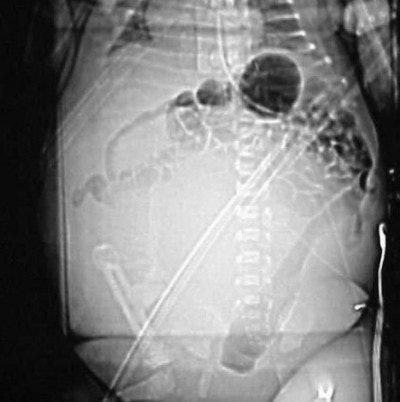

Case 2: The patient is a newborn girl with a large soft-tissue mass extending from her buttocks through her thighs. The scout AP image (Figure CT 12) shows an extensive, rounded soft-tissue mass.

![]() |

| Figure CT 12 |

It is uncommon to use contrast in an infant less than six months old because their kidneys are not yet fully developed. In this case, doctors decided that the benefits were worth the risk of harm, so I used 4 cc of Visipaque (iodixanol, GE Healthcare Bio-Sciences, Buckinghamshire, U.K.) hand-injected through a 24-gauge angiocath with a 20-second delay.

Images (Figures CT 13 and CT 14) show a large, enhancing, soft-tissue mass extending from the buttocks, past the labial folds, and into the thighs. She was diagnosed with a rhabdomyosarcoma that was successfully excised.